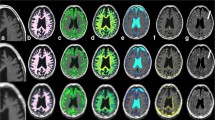

Regions of interest analysis

Segmentations were performed manually using 3D-Slicer software [20] as described in Fig. 1. Four to ten lesions were selected for each patient with MS, with a total of 105 lesions across 18 patients, 10 of which were active lesions. Perilesional edema was not included in the segmentation of active lesions. Additionally, for each patient, one ROI each in F-NAWM and splenium of the corpus callosum were drawn. F-NAWM was defined as areas without signal changes on the standard T2 weighted images in the clinical exam. In the control group, corresponding ROIs were drawn in the F-NAWM and splenium. First order statistics (interquartile range, skewness, uniformity, median, energy, robust mean absolute deviation, mean absolute deviation, total energy, maximum, root mean squared, 90 percentile, minimum, entropy, range, variance, 10 percentile, kurtosis, mean) obtained from each ROI were analyzed. All segmentations were reviewed by a Board certified neuroradiologist.

Region of Interest segmentations within MRF maps: MRF T1 relaxometry map demonstrating an active lesion in a patient with multiple sclerosis. a Depicts the lesion [1] in the parietal white matter and the corresponding ROI. The T1 and T2 values and the first order statistics were simultaneously obtained from this ROI. b shows the ROI over the frontal normal appearing white matter [2] and splenium [3]

Partial least squares discriminant analysis (PLS-DA) for F-NAWM and splenium is displayed in Fig. 3. Repeated cross validation (n = 5) showed mean out-of-fold accuracy = 65 % (AUC = 0.625 (p = 0.21)) for discriminant results between patients and controls for F-NAWM, but mean out-of-fold accuracy approaching 90 % (AUC = 0.880, p < 0.0001) for splenium, primarily via component 1. Examination of the component 1 feature loadings indicated maximum T1 value (-0.30) and T1 robust mean absolute deviation (-0.28). This was commensurate with univariate findings, where the top associations (Table 1) corresponded to T1 distributional measures of extrema (e.g., T1 90 % percentile: Wilcoxon p = 0.002) and variability (e.g., T1 Root Mean Squared: Wilcoxon p = 0.003).

The T-SNE Plot for classification of MS lesions is displayed on Fig. 4. AUC analysis for selected features demonstrated that median and mean T1 and T2 allowed perfect discrimination (AUC = 1) between splenium and lesions for both T1 and T2. Also, discrimination from F-NAWM was excellent (AUC = 1) and (AUC = 0.98) using median and mean for T1 and T2, respectively. Figure 5 depicts the distribution range of mean T1 and T2 relaxometry ranges for all structures analyzed.